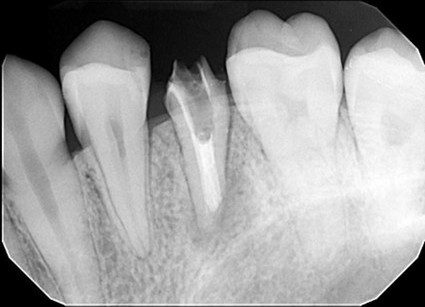

| 主訴 | 膿で腫れて痛みが強い、他の歯医者で抜歯しかないと言われ相談で来院 |

| 状態 | 自発痛もかなり強く、写真のように膿が溜まって腫れ上がっている状態 |

| 治療内容 | X写真から根先部の根先病変が原因と思われるため、根管治療を行った。 骨成長因子を用いて、骨の再生を促した。 結果、2年経過後病変の大きさが1/3まで縮小し、骨の再生が認められる。 本人も症状や違和感がなくなったため、一時的に補綴物をセラミックで行った。 |

| 料金 | 根管治療10万円、ファイバーコア2万円、EーMAX11.5万円 |